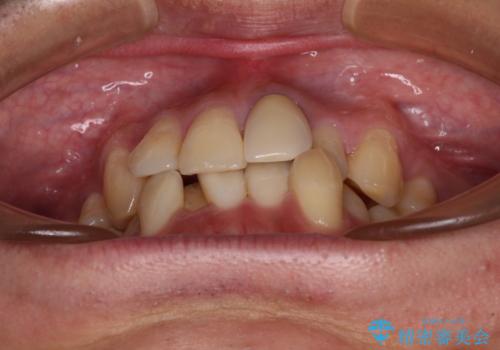

- 下顎の八重歯を気にして来院された患者様です。

左下以外、3本の第一小臼歯が既に抜去されており、左下は八重歯になっている状態でした。

左下の八重歯は手前に傾斜していたため、インビザラインによる抜歯矯正が可能と判断し、後方にある第一小臼歯を抜歯してインビザラインにて矯正治療を行うこととしました。

ワイヤー矯正と比較すると、八重歯が後方に傾斜した仕上がりとなりましたが、患者様ご希望のインビザラインにて十分な歯列を達成することができました。